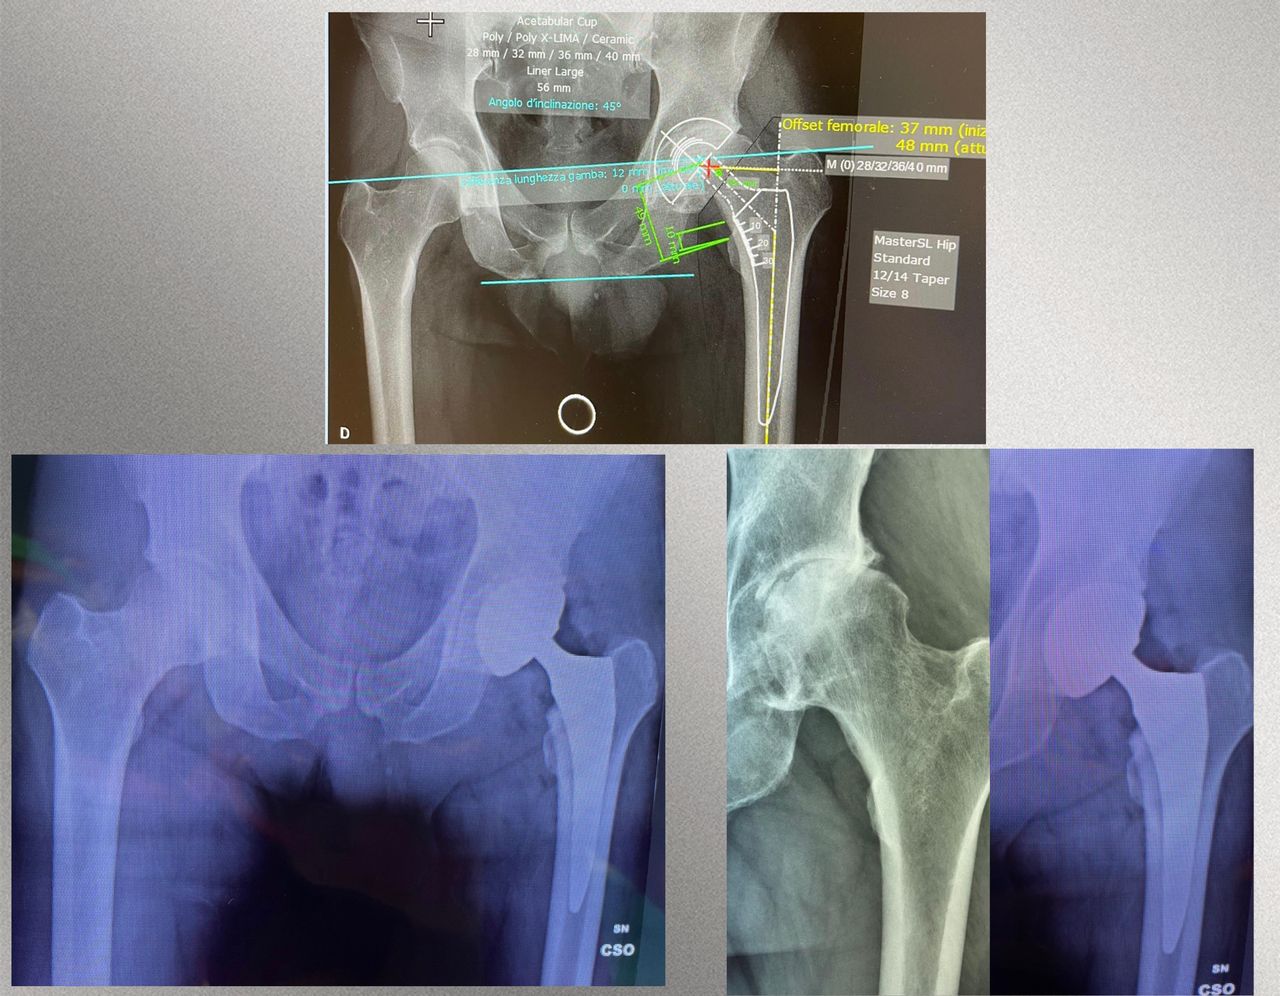

• Chirurgia protesica mini-invasiva di anca e ginocchio a Firenze – interventi eseguiti con approcci che riducono il trauma chirurgico, rispettano i tessuti e favoriscono un recupero più rapido.

• Planning pre-operatorio 2D e 3D – pianificazione computerizzata che assicura la massima precisione nella ricostruzione della biomeccanica articolare.